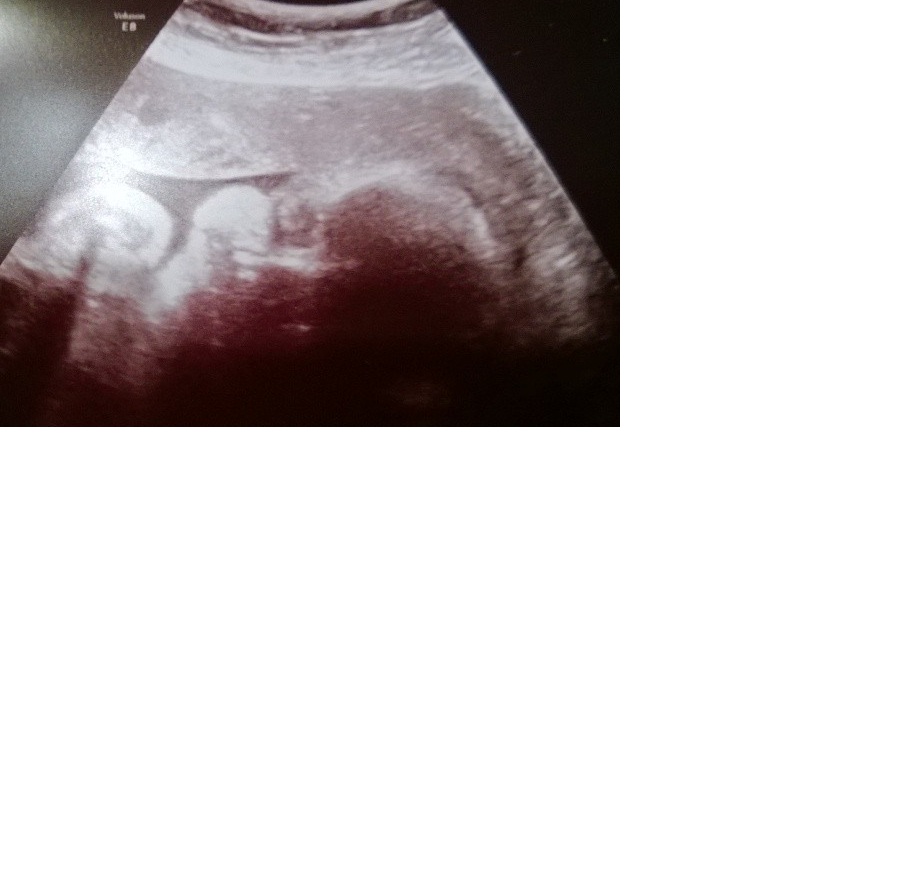

So I had my 31 week growth U/S today. Baby is 4 lbs. 1 oz. and all is looking good. The LO would hardly hold still the whole time and they could see that the baby was practicing breathing a lot which indicates good lung development. They were even able to tell us that the baby already has hair! LOL. The best though was when they got a shot of the face. I could see the chubby cheeks! :-)

Sorry I had to delete the original pic cause I didn't realize all my info was on it. Here is the cropped photo.